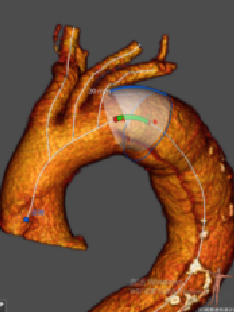

★ 病例3:弓部动脉瘤伴大量附壁血栓

该病例动脉瘤内有大量附壁血栓,一旦术中血栓脱落,可能导致脑梗死或者栓塞。

主体支架顺利通过主动脉弓准确定位释放,各分支依次延导丝进入内嵌通道后释放。治疗效果良好,没有任何卒中和栓塞。